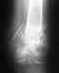

Без рентгенограммы по одному перечислению событий оценить ситуацию невозможно.